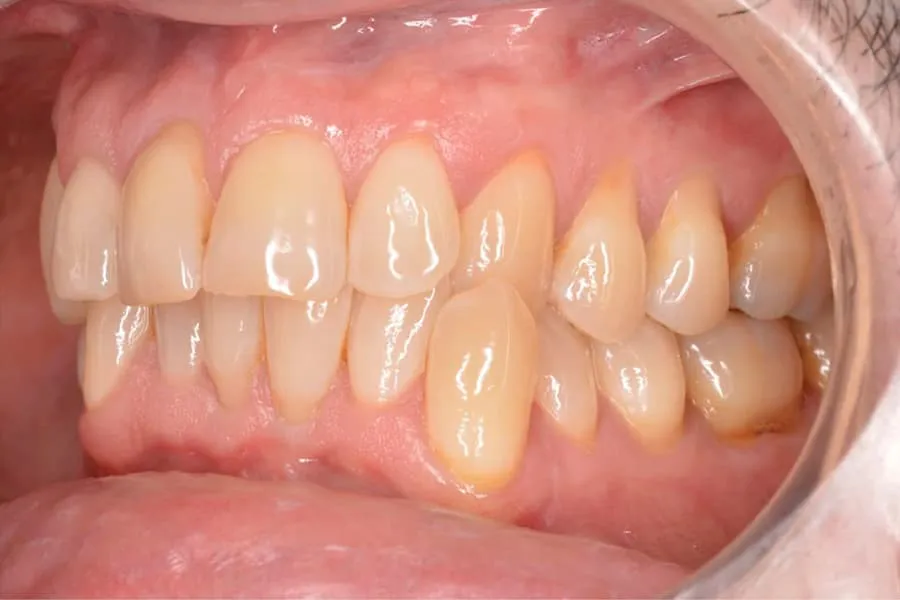

La mordida cruzada anterior se presenta como una maloclusión que altera la alineación habitual de los dientes.

- En la mordida cruzada anterior, los incisivos superiores ocluyen por dentro de los inferiores, mientras que en la sobremordida, los dientes superiores cubren excesivamente a los inferiores.

Tipos de mordida cruzada anterior: Dentaria y esquelética

- Mordida cruzada dentaria: Esta forma se refiere exclusivamente a la malposición de los dientes, sin que haya un desajuste óseo significativo.

- Mordida cruzada esquelética: En este caso, hay un verdadero desajuste en la relación de las estructuras óseas que sostienen los dientes, lo cual puede requerir un tratamiento más complejo.